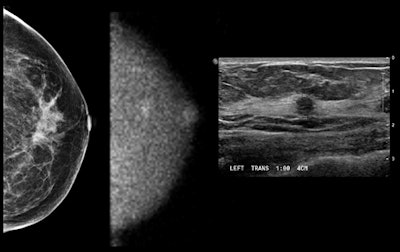

Images show (from left to right) mammogram (craniocaudal view -- read as negative), MBI study (craniocaudal view), and ultrasound study. Patient had an approximately 6-mm invasive cancer of the breast, which is seen on MBI and confirmed by ultrasound and pathology. Patient was a participant in a Mayo Clinic screening study comparing mammography and MBI in women with dense breast tissue. The study was performed using 148 MBq of technetium-99m sestamibi and a 10-minute view. Image courtesy of Michael O'Connor, PhD.